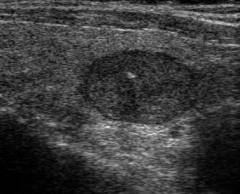

| Ультразвуковое исследование | Визуализирует узел на экране. Оцениваются форма, размеры и консистенция. | Исследование проводится в положении сидя или лежа. Процедура занимает 15-20 минут. |

| Ультразвуковое исследование | Ультразвуковое исследование визуализирует узел в щитовидной железе, позволяя врачу оценить его форму, размеры, консистенцию и расположение. Допплерография и дуплексное сканирование анализируют кровоток в железе и узле. | Исследование проводится сидя или лежа. Пациент откидывает голову назад, врач прикладывает датчик к шее. Процедура занимает 15-20 минут. После исследования пациент получает заключение о состоянии ткани железы и обнаруженных образованиях. |